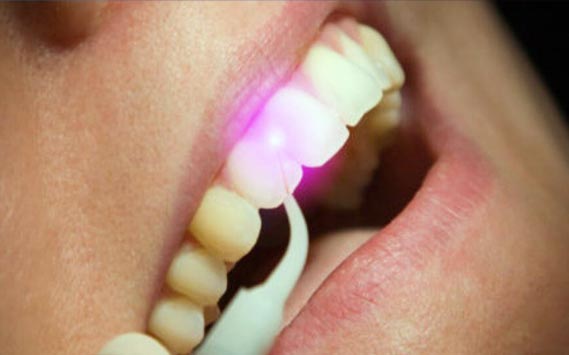

Telecamera laser per diagnosi carie

Grazie alla tecnologia laser totalmente priva di raggi X è possibile individuare la carie anche in fase iniziale. Il principio si basa infatti sulla transilluminazione mediante raggio laser. L’immagine del dente illuminato viene ripresa dalla telecamera ed è visibile sullo schermo di fronte al paziente.

L’utilizzo di questo strumento migliora la capacità di intercettare la carie prima che diventi un problema.